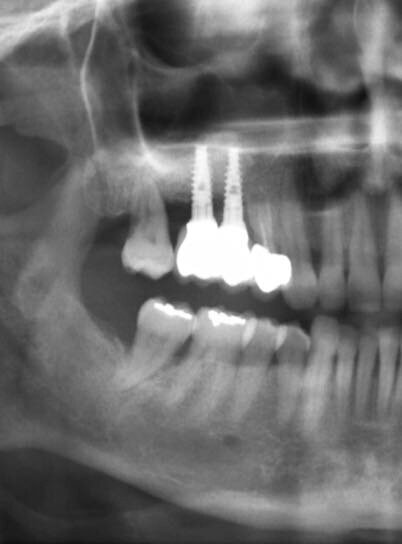

Paziente di sesso femminile, 48 anni, non fumatrice, si rivolge al nostro studio con la richiesta di ripristinare la normale masticazione, ostacolata dall’assenza di due denti precedentemente estratti. L’esame obiettivo evidenzia la mancanza di due elementi dentari nel primo quadrante (1.5 e 1.6). L’anamnesi della paziente è negativa, con un buon livello di igiene e un biotipo gengivale spesso. Viene pertanto prescritta una tomografia computerizzata, CBCT, per valutare il volume di osso disponibile per la riabilitazione (Fig. 1). Analizzando i risultati della CBCT si evince che l’osso basale non è sufficiente a stabilizzare gli impianti necessari per la riabilitazione implanto-protesica e appare ovvia l’esigenza di un aumento dei volumi dello stesso.

Fig. 1_CBCT preoperatoria: si noti la mancanza di osso necessario a stabilizzare due impianti.